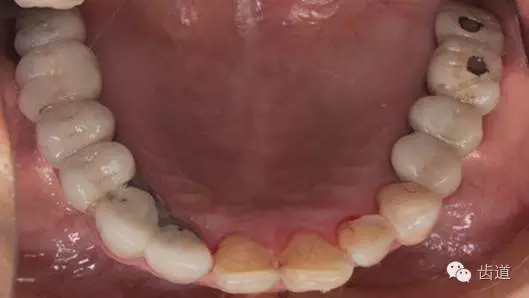

3、下頜牙合面觀

17-12,24-25烤瓷橋修復(fù),邊緣密合可,探-,叩-,松-。

35-38烤瓷橋修復(fù)體,邊緣密合欠佳,探針可探入,探-,叩-,松-。

17,16,26,27,36,37,47缺失。

46,45殘冠,部分白色充填物,繼發(fā)齲壞,探-,叩-,松-。

34遠(yuǎn)中鄰面深齲壞,探+,冷+,叩-,松-。